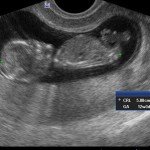

Nei primi mesi di gravidanza, con la misura della lunghezza del feto, è possibile valutare se lo sviluppo corrisponde all’epoca di gravidanza valutata in base alla data dell’ultima mestruazione, il numero dei feti e la presenza dell’attività cardiaca.

Dal secondo trimestre si misurano altre parti fetali, ed i valori di tali misure vengono confrontati con quelli delle curve di riferimento. Si può così valutare la normalità o meno della crescita fetale. Inoltre periodo si visualizzano la sede di inserzione placentare e la quantità di liquido amniotico.